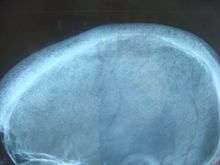

- increased bone resorption, allowing flow of calcium from bone to blood

- reduced kidney clearance of calcium

- increased intestinal calcium absorption

Lack of vitamin D leads to reduced calcium absorption by the intestine leading to hypocalcemia and increased parathyroid hormone secretion. This increases bone resorption. In chronic kidney failure the problem is more specifically failure to convert vitamin D to its active form in the kidney. The bone disease in secondary hyperparathyroidism caused by renal failure is termed renal osteodystrophy.